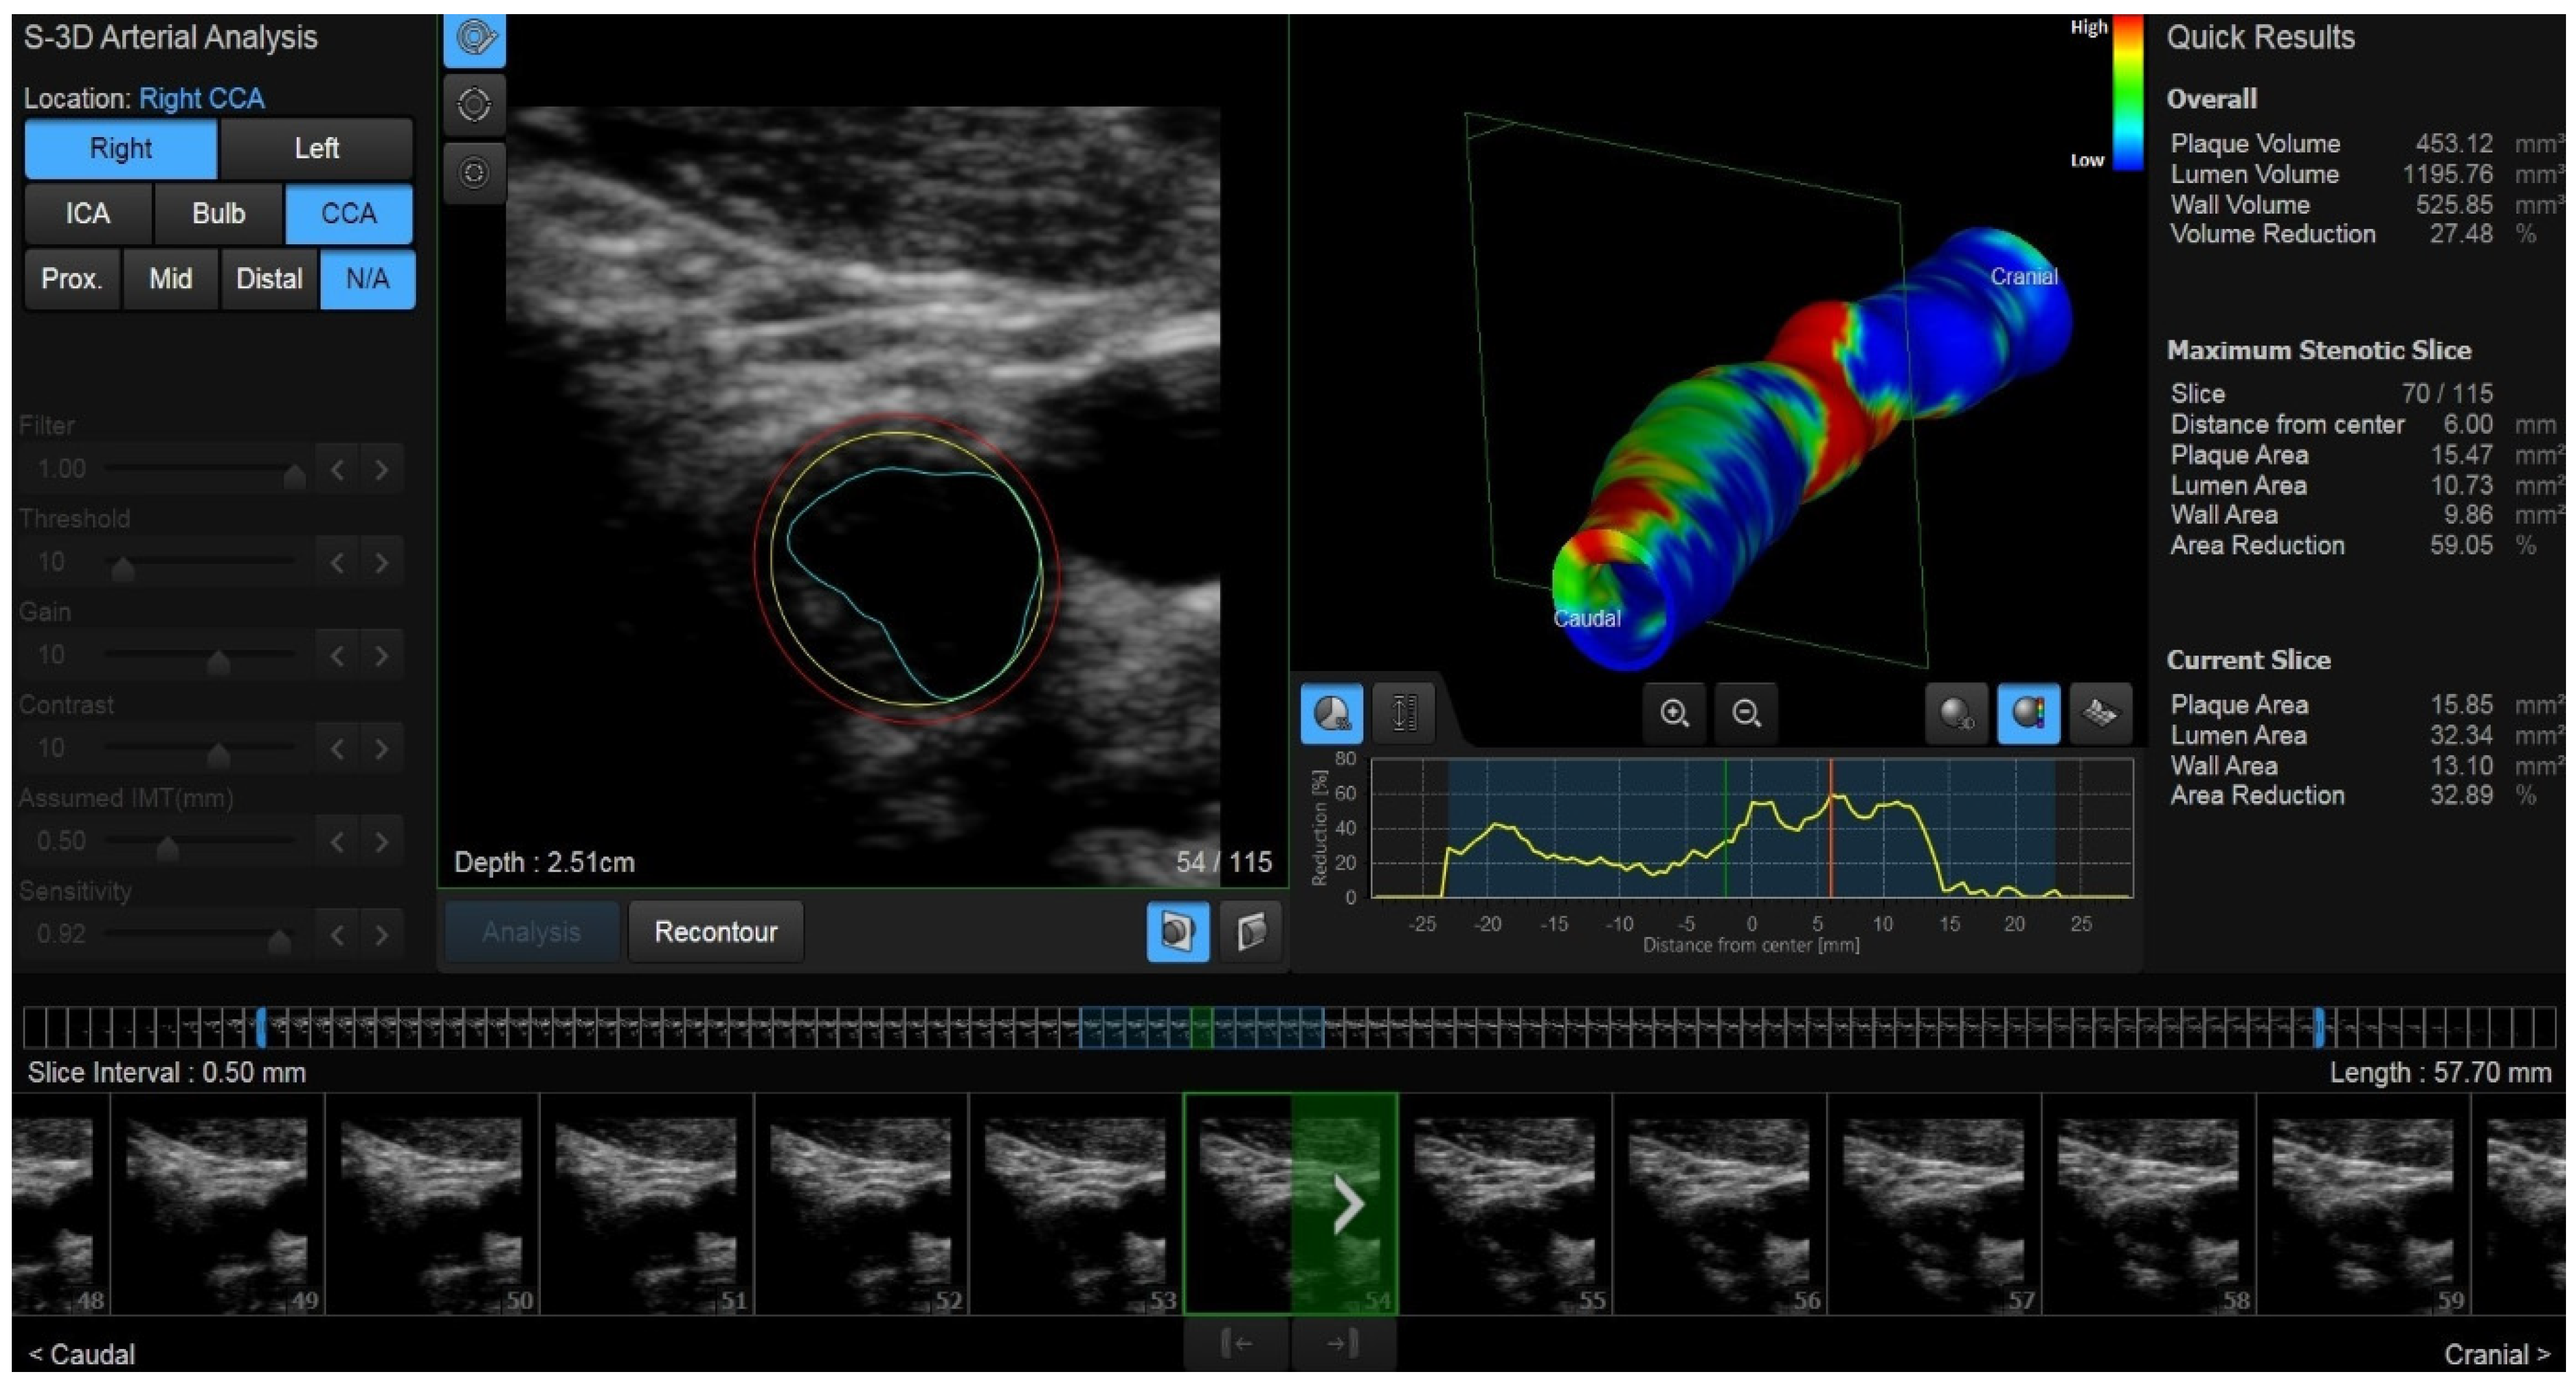

1. Introduction

2.3. New Ultrasound Developments: 3D US and Vector Flow